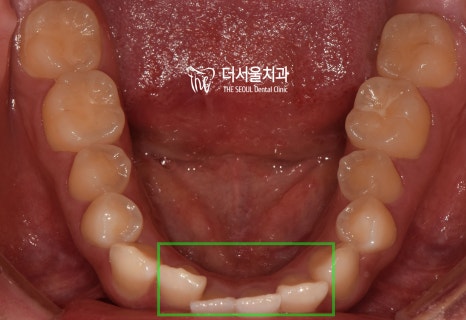

과연 구치부의 상태는 어떨까요?

교합면에서 확인해 보았더니

U자에 가까워야 될 악궁의 형태가

사각형에 가까워져 있었습니다.

하악 앞니 뻗침은 생각보다 심하네요.